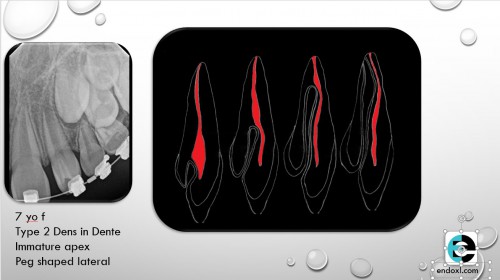

Dens Invaginatus and Regenerative Endodontics on a 7 year old

By Rajiv Patel / August 27, 2018